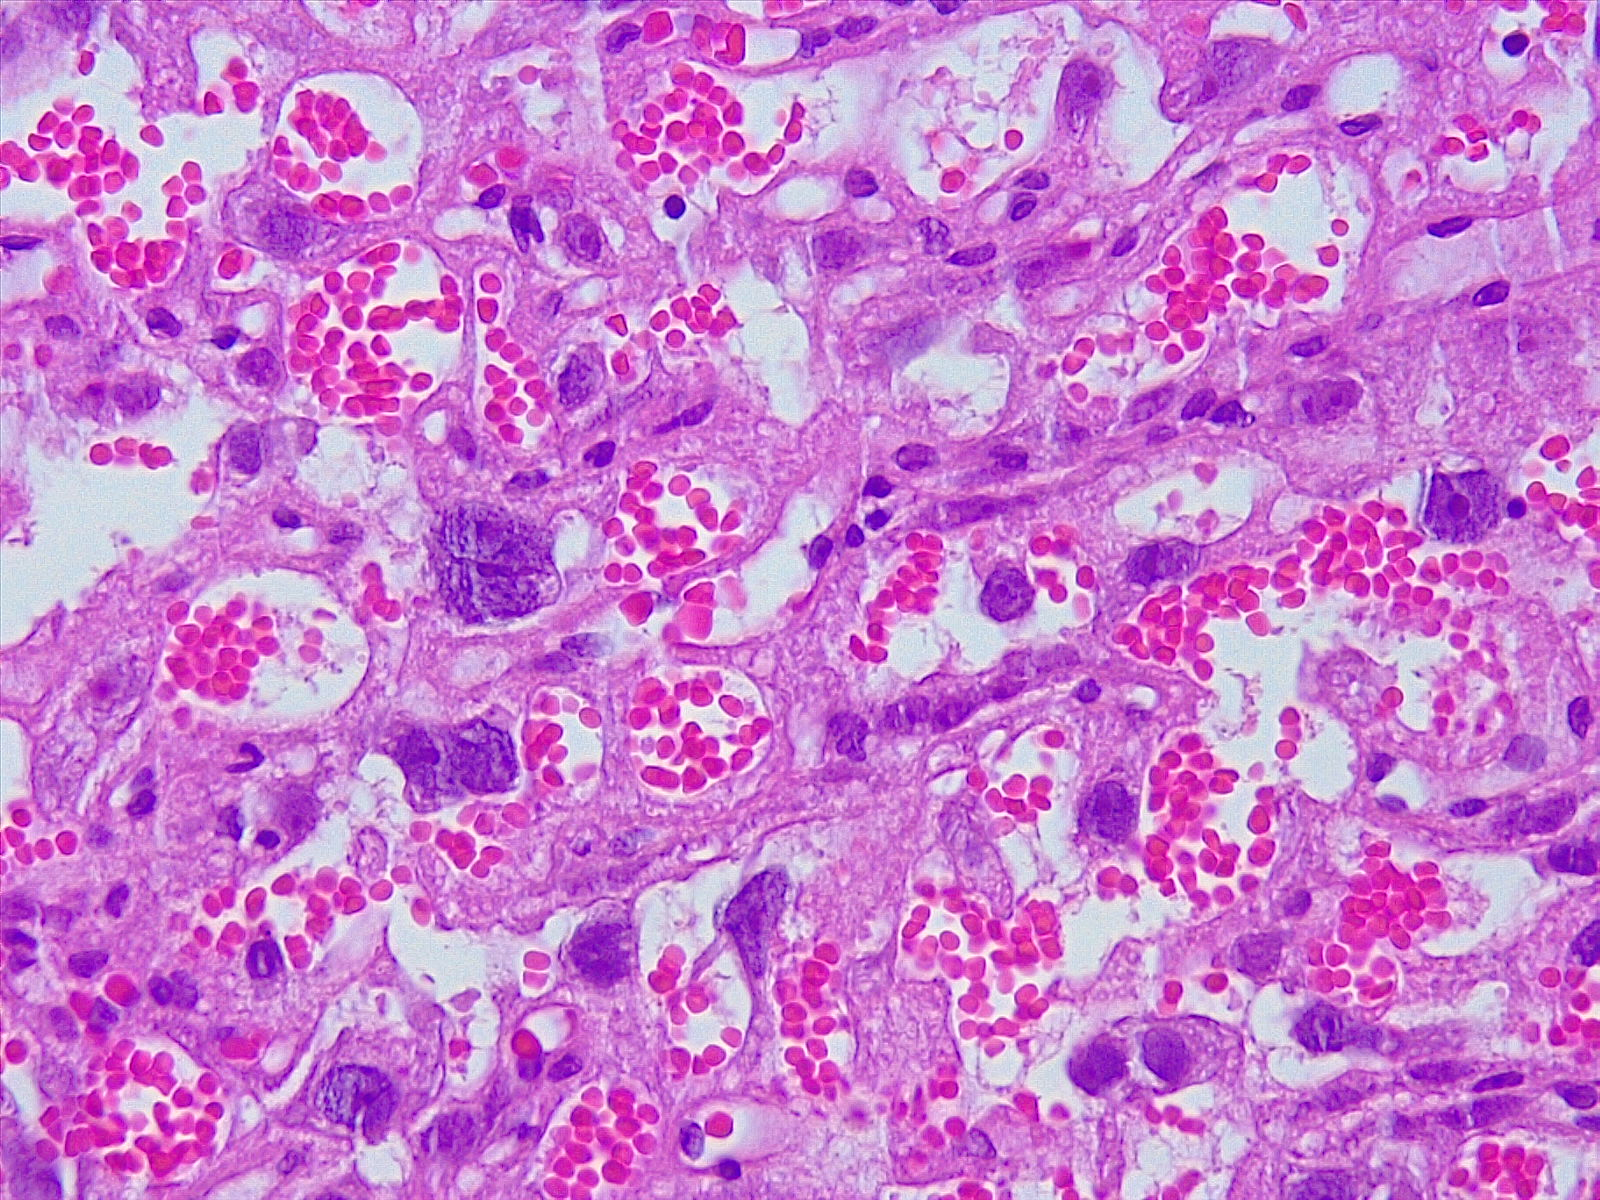

Frente a este punto, la profesora Francisca Villaroel menciona que “El Propedéutico es una instancia súper enriquecedora para los estudiantes, porque les permite acercarse a la vida universitaria a través de los diversos módulos, pero además es una instancia en la que pueden acceder a implementos que quizás en muchos colegios no hay por la falta de laboratorios, por ejemplo microscopios”.

Francisca Villarroel expresó que “he visto mucha motivación de los estudiantes por aprender ciencias, conocer cómo se forma nuestro cuerpo, además de mucho agradecimiento de ellos por la actividad, ya que para muchos era la primera vez que utilizaban un microscopio y podían observar muestras histológicas en el caso de mi módulo”.